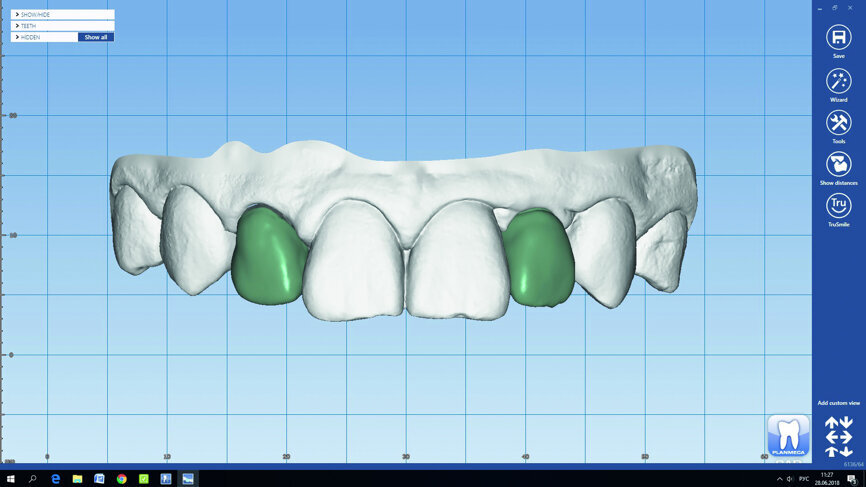

Fig. 14: The final restorations were designed in Planmeca PlanCAD Premium.

Fig. 15: The final restorations were designed in Planmeca PlanCAD Premium.

Fig. 16: The final restorations were designed in Planmeca PlanCAD Premium.

Fig. 17: The final restorations were designed in Planmeca PlanCAD Premium.

Fig. 18: The final restorations were designed in Planmeca PlanCAD Premium.

Fig. 19: The final restorations were designed in Planmeca PlanCAD Premium.

Once the formation of the soft tissues was complete, tooth #12 was minimally prepared for the ceramic crown with the help of a surgical microscope. After the preparation, the teeth were scanned in order to digitally design a custom abutment and crowns (Figs. 14–19).

The final smile design was planned digitally together with the patient. For the implant structure, we chose an individual zirconium abutment screw with a ceramic facing and a fully anatomical Empress crown (Figs. 20 & 21).